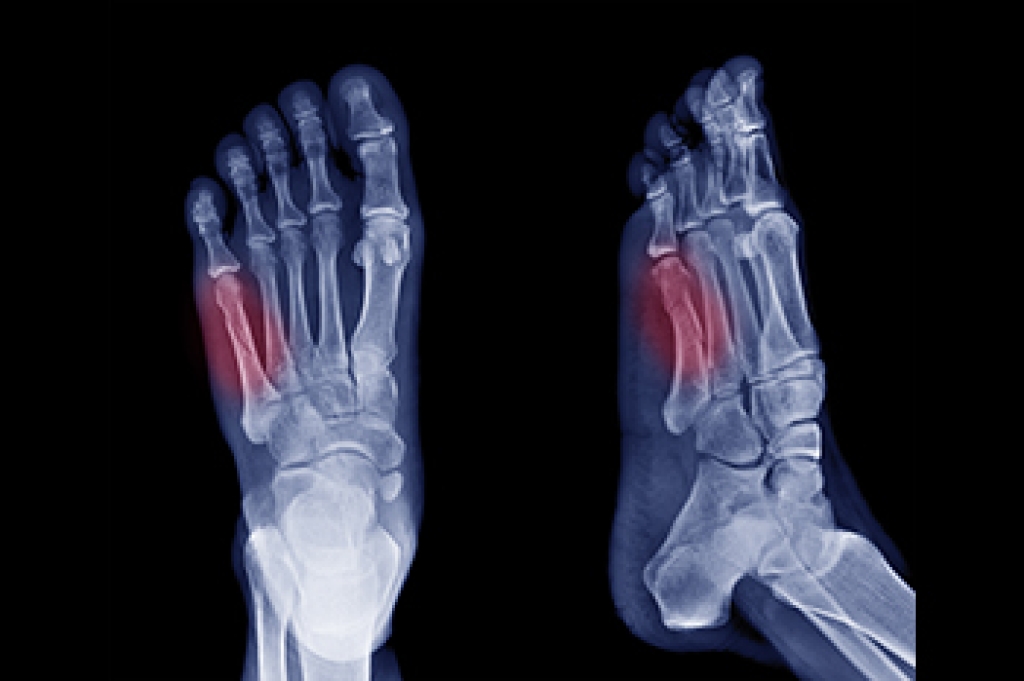

A bunionette, or tailor’s bunion, is a bony prominence on the outer side of the foot at the base of the fifth toe. It develops due to pressure, improper footwear, genetics, or structural foot abnormalities. This condition often affects individuals who wear narrow or tight shoes, such as high heels, or those with naturally wide feet. Conservative treatments, including wider footwear, padding, orthotics, and anti-inflammatory medications, can help reduce discomfort. However, if pain persists despite these measures, minimally invasive bunionette surgery may be an option. This procedure involves tiny incisions and specialized instruments to realign the bone, removing pressure on the affected joint with minimal tissue disruption. Recovery is typically faster than traditional surgery, with reduced swelling and pain. If a bunionette is interfering with your daily activities, it is suggested that you consult a podiatrist to determine if minimally invasive surgery is the right solution for you.

- Removing foot deformities like bunions and bone spurs

- Bunionectomy for painful bunions